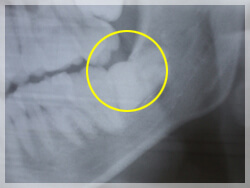

これはどんな症例かわかりますか?

- 術前

- 術後

7番(親知らずの隣)の歯の根尖病巣がひどく、8番(親知らずの歯)と合わせて2本抜き、

8番の親知らずを7番に移植しています。

術後は5年後の状態です。5年経ってもきれいに維持できています。